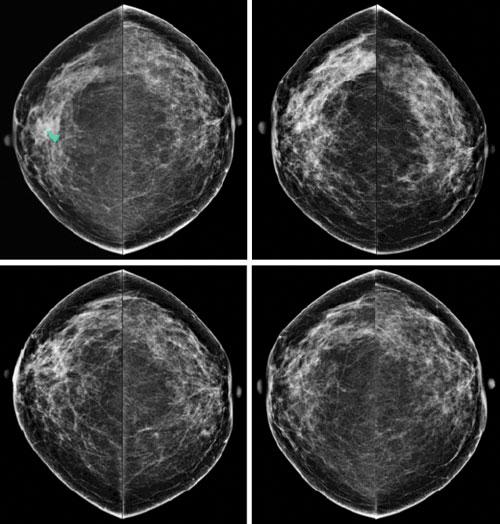

What Does Breast Cancer Look Like On An Mri / Tukn8mabzjjemm / (1) gary ulaner, md, phd, facnm.. Palpation of benign breast masses. This is why we ask questions about menstrual cycle and hormone therapies prior to your study. You may notice dimpling or pitting, and the skin on your breast. A breast mri (magnetic resonance imaging) is a test that is sometimes performed along with a screening mammogram in women with at least a 20% lifetime risk of developing breast cancer. A breast mri usually is performed after you have a biopsy that's.

If these tests don't answer the quest. But not every woman who has been diagnosed with breast cancer needs a breast mri. Determining the extent of cancer after a new breast cancer diagnosis. It can also help detect breast cancer in women with breast implants and in younger women who tend to have dense breast tissue. An mri can be used to look for a disease, such as breast cancer. But there are also other reasons to have a breast mri. Inflammatory breast cancer affects breast tissue and can appear unusually dimpled or thick. Breast mri images are combined, using a computer, to create detailed pictures. A waiver of informed consent Mri scan is also used in breast screening for young women who are at higher risk of developing cancer. Dcis on mri may create an area of irregular enhancement of the mri dye into the breast. They're often easy to move around (mobile) and may be tender. A breast mri is a highly effective test.

Breast Masses Cancerous Tumor Or Benign Lump from www.verywellhealth.com Dcis on mri may create an area of irregular enhancement of the mri dye into the breast. This means that the test finds a mass or other change that seems to show cancer but it is not cancer. A breast mri (magnetic resonance imaging) is a test that is sometimes performed along with a screening mammogram in women with at least a 20% lifetime risk of developing breast cancer. Your doctor may recommend a breast mri for the following: Need to have physical exam, mammogram, and ultrasound as needed. What does breast cancer look like on a mammogram? A breast mri is a highly effective test. Mri scan is also used in breast screening for young women who are at higher risk of developing cancer.

Patients who had baseline breast mri, mammography, and ultrasound examinations were included in this study; The skin looks like the skin of an orange, and may be discolored with painful and itchy breast. By comparison, only 11 out of 48 patients, or 23 percent, with all fatty hilum in place had cancer. Some benign conditions such as fibrocystic disease can look like cancer. Your doctor may recommend a breast mri for the following: